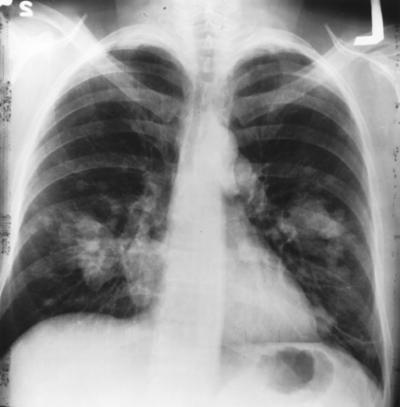

An international group of scientists has identified three genetic regions that predispose Asian women who have never smoked to lung cancer. The finding provides further evidence that risk of lung cancer among never-smokers, especially Asian women, may be associated with certain unique inherited genetic characteristics that distinguishes it from lung cancer in smokers.

Lung cancer in never-smokers is the seventh leading cause of cancer deaths worldwide, and the majority of lung cancers diagnosed historically among women in Eastern Asia have been in women who never smoked. The specific genetic variations found in this study had not been associated with lung cancer risk in other populations.